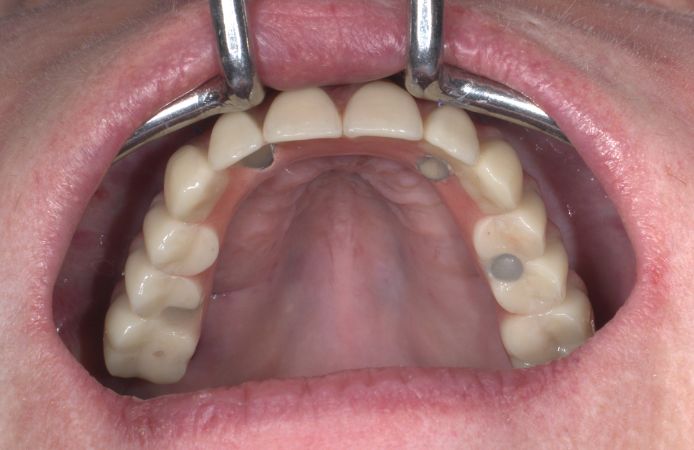

Figure 1.

Initial clinical situation with existing telescopic bridge in place in the upper jaw.

Figure 2.

Initial clinical situation after removal of failing telescopic bridge.